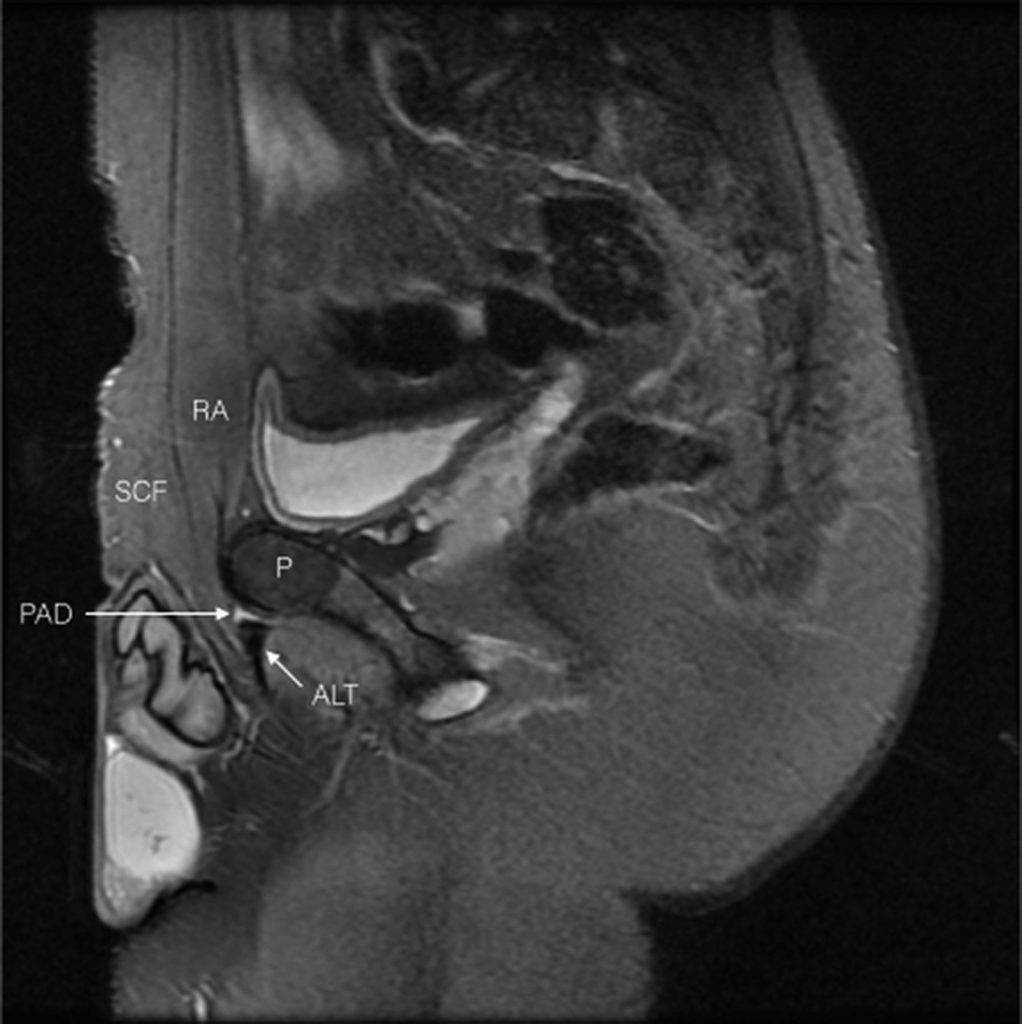

Картина МРТ при пубалгии

Визуализирующие методы исследования очень важны для такого сложного диагноза как пубалгия. Помочь с постановкой диагноза могут УЗИ, МРТ, КТ, контрастная рентгенография грыжи и лапороскопия.

МРТ может показать патологические изменения в миофасциальных слоях брюшной стенки, что тесно коррелирует с данными, полученными в результате хирургического вмешательства. МРТ также может обнаружить отек в области лобкового симфиза, вызванный дисбалансом сил и искаженным движением сустава.